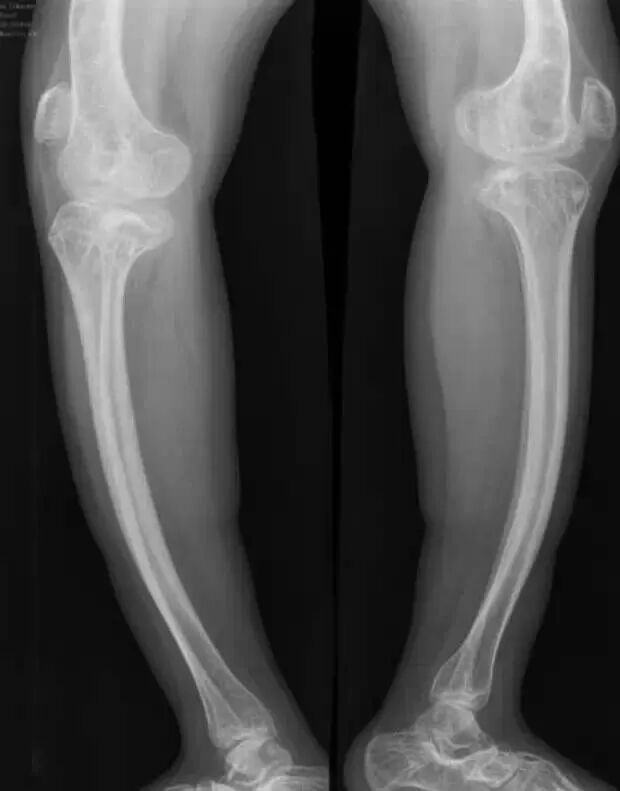

入院检查:患者男性,16岁,因“外伤致右大腿肿痛伴活动受限2天”;体查:平时坐轮椅生活,身高: 132cm,体重: 43kg,蓝巩膜,双下肢弯曲畸形,X形腿右下肢石膏固定,右大腿稍肿胀,压痛,可及骨擦感。辅查:本院X线及CT(见图一):右股骨干下段骨折,骨质疏松,双下肢弯曲畸形,胸片及ECG无明显异常;其他:既往史无特殊,父母及1兄弟均无遗传病史。

图一:入院X线及CT

入院诊断:1.右侧股骨干下段骨折伴双下肢畸形2.成骨不全症 3.继发性骨质疏松